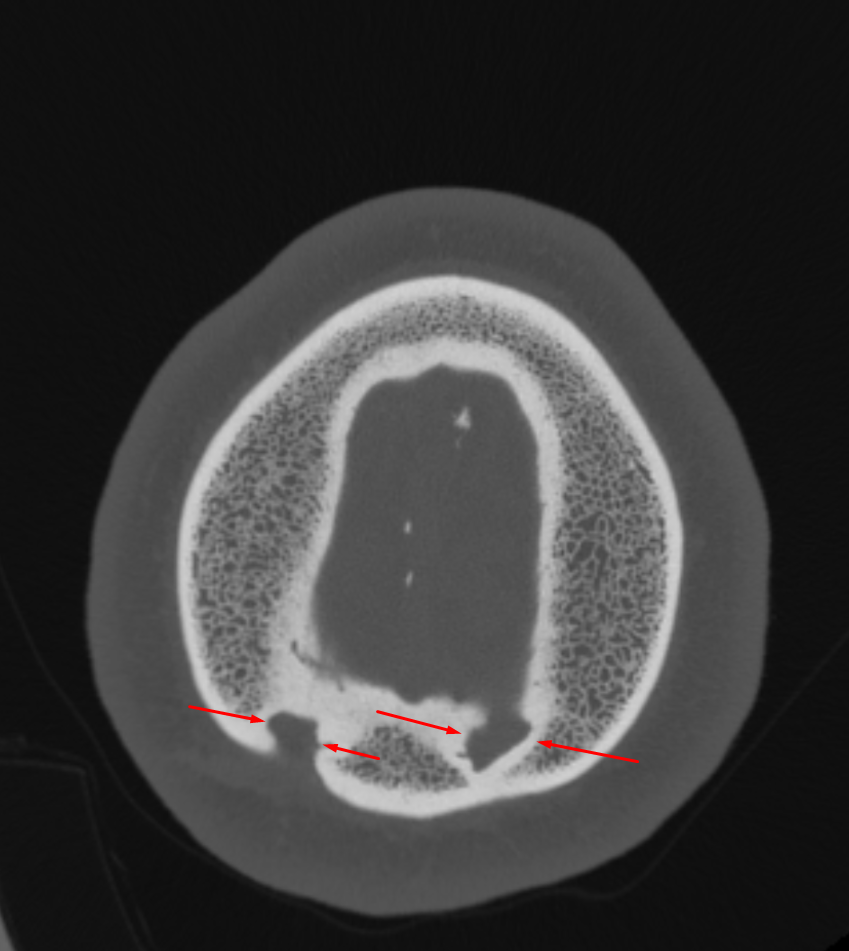

Age: 46

Sex: Male

Indication: Scalp Wound